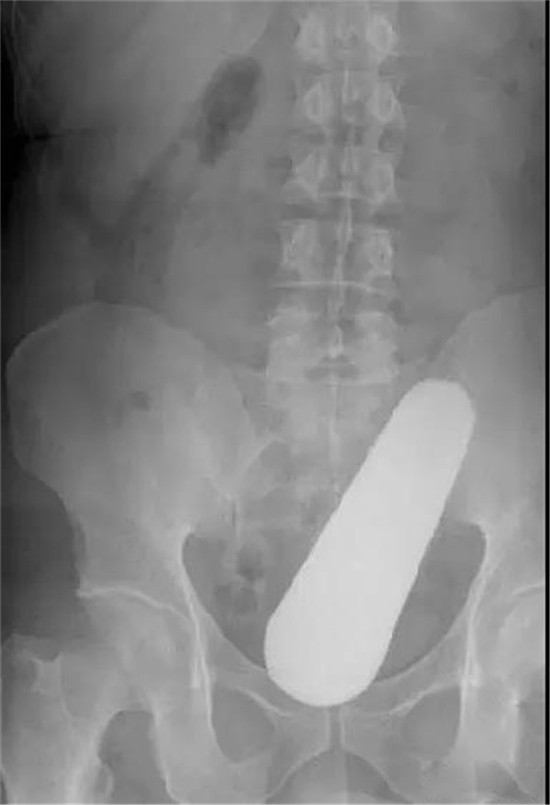

大肠里的擀面杖。男性

这是做饺子皮用的擀面杖。对,全部塞进去了。你知道怎么看男女吗?看骨盆的角度。

取出的方法如同上面。